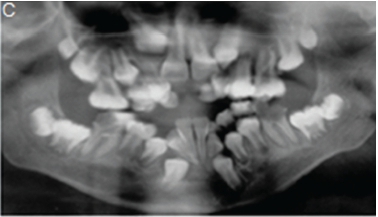

A diagnosis of Apert syndrome was made. Apert syndrome is a rare developmental condition characterized by premature cranial synostosis and resultant growth disturbances. Signs of Apert syndrome include a peaked and vertically elongated head, widespread bulging eyes, and a protuberant frontal region with an anteroposterior ridge overhanging the frontal eminence (Figure A). The palate is high, arched and occasionally cleft (Figure B). There is hypoplasia of the maxilla with relative prognatism of the mandible. Dental malocclusions with crowding and delayed dental eruption in the maxilla are common (Figure C). The facial angle is exaggerated; the nose is small and has been compared to a parrot's beak in appearance. Hypertelorism, exophthalmos and divergent strabismus are often present; sometimes with blindness. Spina bifida has been recorded in some patients. Syndactyly of the hands and feet varies greatly. Hand films in Apert syndrome showing syndactyly with fusion of three fingers in both hands and webbing (Figure D). Syndactyly of the feet in the same patient is also discernible (Figure E) Note the tall (turricephalic) skull, open metopic suture, and faint beaten-silver appearance of the calvarium. Skull base and roof of the calvarium are flattened, with a noticeable beaten-silver appearance (Figure F). The 3-D CT reconstruction of the same patient showing hypoplastic maxilla with posterior cleft (Figure G) The patient may be retarded or of normal intelligence. Apert syndrome may be associated with advanced paternal age. The cardinal radiologic features of Apert syndrome are: Brachycephalic (reduced anteroposterior dimension of the skull with increased skull width). Turricephaly (occurrence of a skull with high vertical index), beaten silver appearance of the calvarium, absence of demonstrable cranial sutures in coronal dimension in young patients, hypoplastic maxilla and syndactyly of the hands and feet. Differential Diagnosis: Crouzon's disease, Pfeifer syndrome, Carpenter syndrome and Summit syndrome.